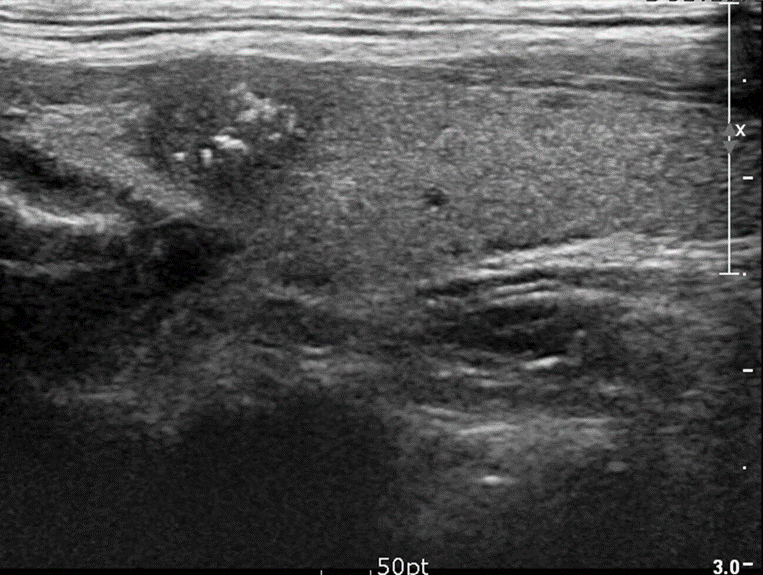

A-Solid thyroid nodule with microcalcifications

Ultrasound thyroid (longitudinal plane) A solid nodule in the upper pole has ill-defined margins and contains multiple microcalcifications.

The presence of microcalcifications increases suspicion for malignancy